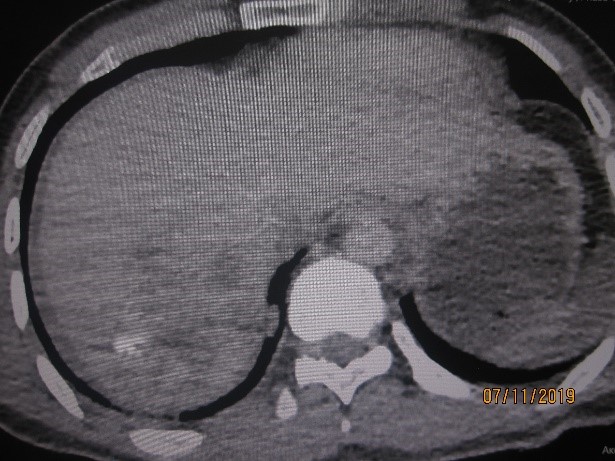

МЕТОДЫ И МАТЕРИАЛЫ. Проанализированы результаты лечения 76 пострадавших с закрытыми травмами печени, получавшим традиционное лечение, и 78, которым лечение проводили в соответствии с разработанным новым алгоритмом. Во второй группе пациентам с УЗИ с признаками разрывов печени и стабильной гемодинамикой (сист. АД>90 мм рт. ст.) выполняли МСКТ с внутривенным контрастированием. При отсутствии признаков продолжающегося кровотечения осуществляли консервативное лечение, при их выявлении – ангиографию с селективной ангиоэмболизацией.

РЕЗУЛЬТАТЫ. Статистически значимых различий по полу, возрасту, механизму и тяжести травмы (по шкалам ISS, Ю. Н. Цибина, ВПХ-П) и тяжести состояния (ВПХ-СП) между пациентами групп не выявлено. Более половины (52,3 %) пострадавших основной группы пролечено без оперативных вмешательств на органах живота. При использовании предложенного алгоритма у пациентов со стабильной гемодинамикой лапароцентез уступил место менее травматичным и более точным методам диагностики внутрибрюшных кровотечений. Все лапаротомии в основной группе были выполнены по поводу других повреждений органов живота. У пострадавших обеих групп видеолапароскопия носила диагностический характер. Одному пациенту основной группы с повреждением печени IV степени по шкале AAST с продолжающимся внутрипаренхиматозным и внутрибрюшным кровотечением проведен эндоваскулярный гемостаз.